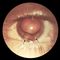

При туберкулезе мочевого пузыря вначале больные могут жаловаться на учащенное днем и ночью мочеиспускание, в дальнейшем с прогрессированием болезни оно становится болезненным и еще более частым. При цистоскопии в начальной стадии болезни обнаруживают ограниченные участки гиперемии на фоне неизмененной слизистой оболочки, позднее по ходу отдельных сосудов выявляются единичные желтые туберкулезные гранулемы, окруженные тонким поясом гиперемии. При дальнейшем прогрессировании процесса на слизистой оболочке мочевого пузыря образуются язвы, захватывающие и более глубокие слои его стенки. При своевременно начатой противотуберкулезной терапии очаги гиперемии и гранулемы быстро регрессируют, туберкулезную природу патологического процесса в этом случае можно подтвердить с помощью эндовезикальной биопсии слизистой оболочки мочевого пузыря с подслизистой основой.